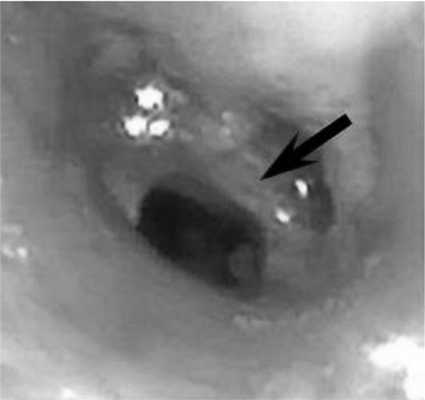

Рис. 3. Формирующийся стеноз промежуточного бронха. Рубцовое сужение диаметром 4 мм, протяженностью 5-6 мм (указано стрелкой).